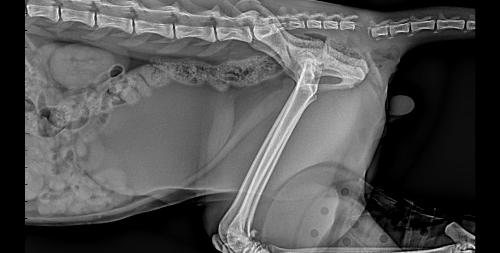

Come steccare una frattura nel gattto. Frattura di femore che si ricompone con mezzo di fissità interno.

Frattura , lussazione falange zampa posteriore sx. Frattura del femore nel gatto. Cure rimedi naturali frattura ossea nel gatto omeopatia inizialmente, a seguito di un trauma il rimedio consigliato è arnica comp della heel. .foto frattura frattura bacino frattura dente frattura mandibola frattura ulna frattura unghia frattura zampa fratture sanitario wustel york shire yorkshire zampa zampa gonfia zampe zampe posteriori zecca zecche zoonosi zoppia zoppie. Soccorso per problemi concomitanti causati dal trauma è la parte più importante del trattamento. Maddy ha il gatto che è stato investito e vuole sapere cosa deve fare, per questo ha chiesto aiuto nella tua lettera ci dici che il micio è stato investito e da allora non poggia più la zampina posteriore. Una lussazione non è visibile come un frattura ma riduce nel gatto la sua capacità di sopportare il suo peso. La frattura del femore è una delle più comuni nel gatto. Il proprietario riferiva che il gatto, rientrato dopo qualche giorno di assenza, probabilmente aveva patito la caduta da un muro di cinta di notevole. Trattamento del metatarso e metacarpo fratture in gatti. Problemi neurologici come deficit propriocettivi; Si chiama borsa primordiale, e ha funzioni precise. A volte, gatti e umani, dobbiamo andare nel nostro giardino segreto. Mao mao è stato trattato alla clinica veterinaria parabiago. Illustrazione dell'icona del fumetto della maschera da portare del gatto fortunato sveglio. Come steccare una frattura nel gattto. Vi siete mai chiesti perché il cane alza la zampa posteriore?